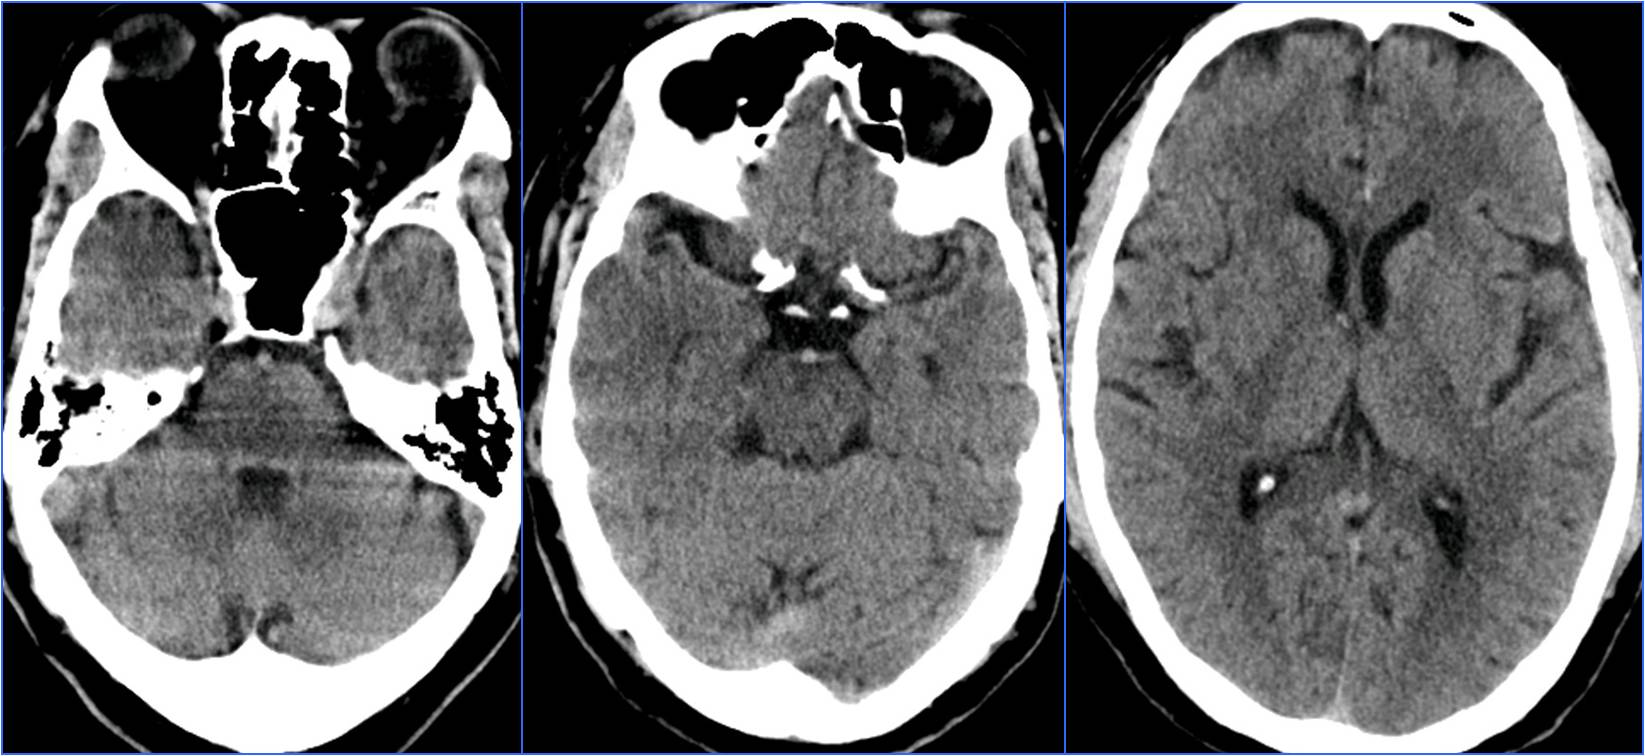

▼7:22头CT

▼8:36头MRA

▼9:19头CT

▼11:11复查头CT

▼11:56头MRA